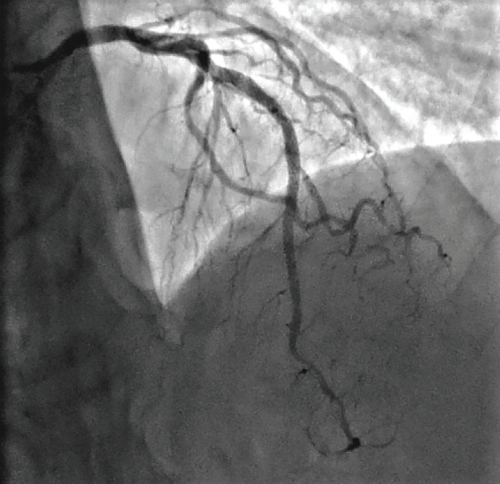

Like all centers, we are using more and more advanced imaging, but it is not uncommon for a lesion to be unpredictably difficult to dilate and more heavily calcified than is readily apparent on angiography. In those situations, with a lesion that will not dilate, it is necessary to have a method by which to modify the calcium, even though its presence was not anticipated. This is a particularly precarious situation for operators in non-backup settings. In the past, we would use oversized, non-compliant balloons and take them to very high pressures trying to achieve an adequate final stent result. In exceptionally rare cases, a handful of times over my 10 years here, we would even abort the case mid angioplasty and have to transfer the patient in a less than entirely stable fashion to the high-risk center. Calcium was our Achilles’ heel. We could always filter out the obviously high-risk cases, but there will always be a very small fraction of cases that do not have readily apparent calcium and are non-dilatable. IVL, from a safety standpoint, has been a game-changer for us not only in these cases, but also for cases with readily apparent calcium that otherwise would have required atherectomy. With the use of IVL, we are now at a point where the only cases that we have to either transfer or stage are non-crossable lesions: cases where you can get a wire but not a balloon across, and these are fairly rare.

While the extent of calcium might not be apparent on angiography, if you do see calcium, what happens next?

With the ability to more aggressively treat calcium here at our primary site with IVL, there has been a big uptick in our utilization of intervascular imaging such as intravascular ultrasound (IVUS). We are bringing in optical coherence tomography (OCT), with the idea that we will image a much higher fraction of our cases, because of this concept of unappreciated calcification. When we see either moderate or worse calcium, or have a recalcitrant lesion or lesion that is not dilating normally, we are quick to pull the IVUS imaging catheter out in order to assess the arc, length, and width of the calcium. Post IVL, we will generally reassess the lesion to confirm fracture of the calcium. We don’t require IVUS post IVL for stenting, but it definitely is something that makes us feel good about moving forward with stent implantation. More and more, intravascular imaging is going to be a marketable quality indicator. If you are only doing a small percentage of intravascular imaging, I think you are going to be perceived as a lesser quality program. There has been a longstanding resistance to adopting a higher utilization of intravascular imaging, because of the combination of cost and time. I wish that CMS would see the benefit and create a situation where there are not negative financial incentives to doing imaging.